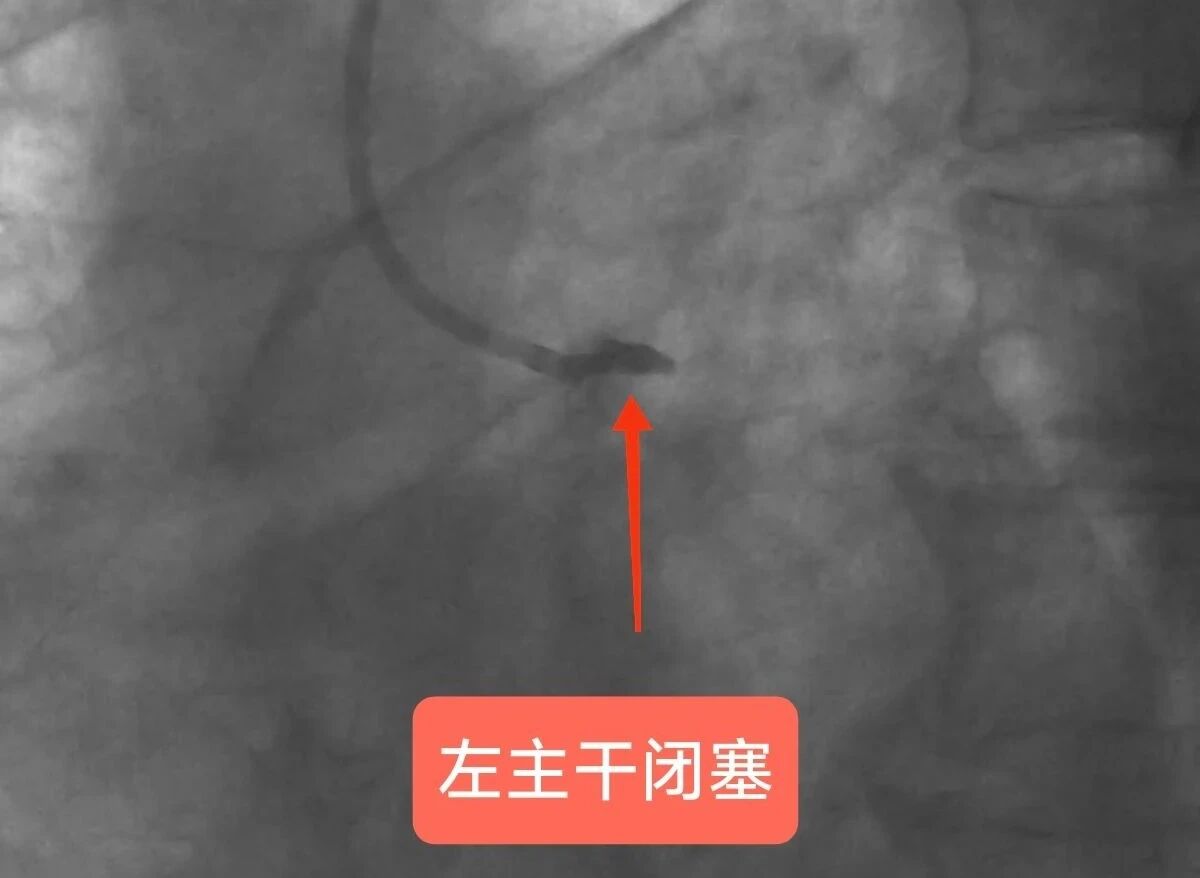

玉溪市人民医院派驻心内科专家李驹、玉溪市中山医院心内科副主任李国辉团队紧急启动手术。术中,李驹指导实施急诊PCI手术,迅速打通钟先生堵塞血管,并植入支架及时恢复心脏血液供应。由于钟先生常规穿刺部位的血管条件不佳,李驹便从大腿根部血管(股动脉)用超声引导插入导管进行冠脉造影,造影发现钟先生心脏核心血管——左主干急性完全堵塞,其他分支血管也堵塞严重,心脏几乎得不到供血,随时可能心跳停止。

冠脉造影显示患者左主干血管闭塞